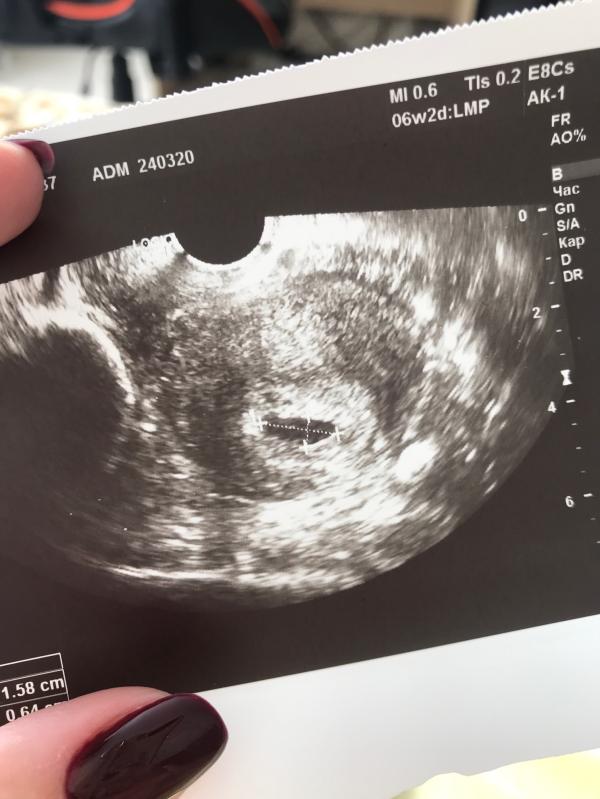

Ровно год назад с этого теста началась наша с Денисом пока ещё маленькая семейная история 🤍🐣

Помню, как с трясущимися руками разбудила мужа и дрожащим голосом сказала, что беременна. Помню первые узи, сюрпризы для близких, как медленно рос животик, пиночки.. чудесное было время ✨